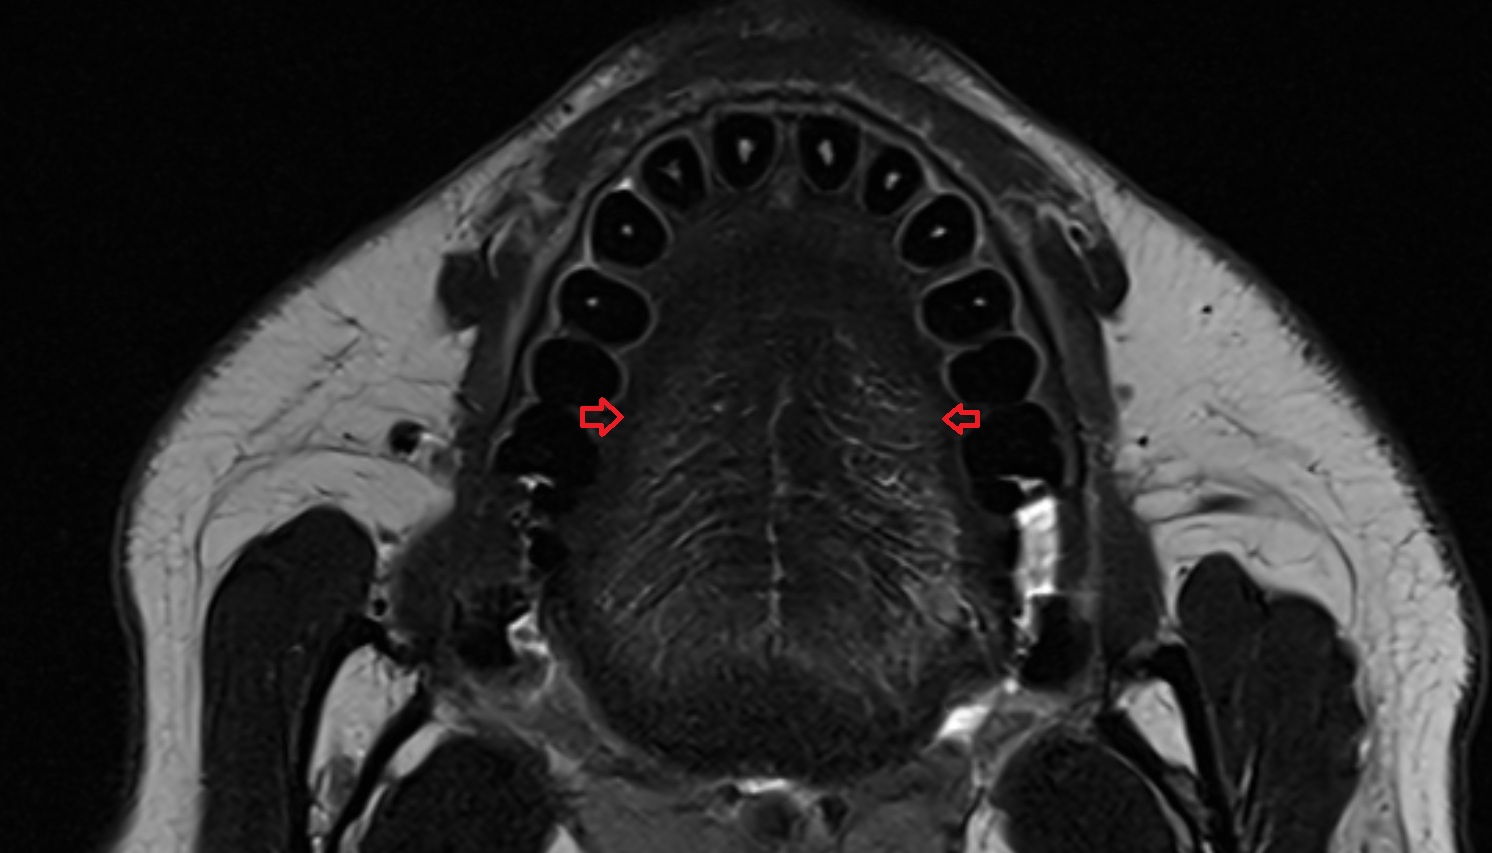

- Temporomandibular joint

- Mandibular condyle

- Mandibular fossa

- Lateral pterygoid muscle

- Medial pterygoid muscle